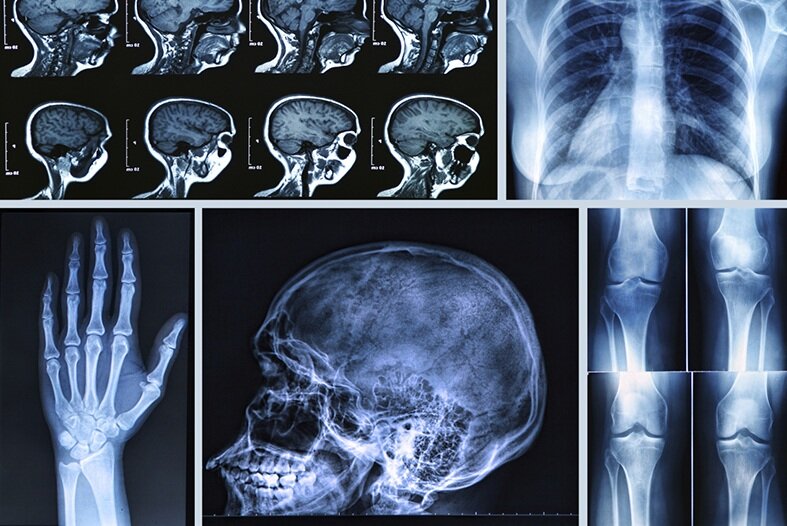

رادیوگرافی به فرآیند فنی تهیه تصاویر پزشکی با استفاده از اشعه ایکس اطلاق میشود که توسط تکنسینهای متخصص انجام شده و صرفاً شامل ثبت تصویر است، در حالی که رادیولوژی شاخهای تخصصی از پزشکی است که شامل تفسیر، تحلیل و بهرهبرداری بالینی از این تصاویر و سایر روشهای پیشرفته مانند سیتی اسکن، امآرآی و سونوگرافی میشود و توسط پزشکان متخصص رادیولوژی انجام میگیرد. در این مطلب بهصورت تخصصی به تفاوت رادیولوژی و رادیوگرافی، صلاحیتهای پزشک رادیولوژیست و سادهترین راه گرفتن نوبت رادیولوژیست آنلاین میپردازیم.

رادیوگرافی عمدتاً به استفاده از اشعه ایکس برای گرفتن تصاویر ساده و اولیه محدود میشود که به آن رادیوگرافی یا اشعه ایکس گفته میشود. این تصاویر پایهای برای تشخیص بسیاری از مشکلات مانند شکستگیها و بیماریهای استخوانی هستند و توسط تکنسینهای رادیوگرافی تهیه میشوند.

رادیولوژی اما شامل طیف وسیعی از فناوریهای تصویربرداری است که فراتر از اشعه ایکس ساده است. این فناوریها شامل سیتی اسکن (CT)، تصویربرداری رزونانس مغناطیسی (MRI)، سونوگرافی، پزشکی هستهای و روشهای رادیولوژی مداخلهای میشود. هر کدام از این روشها کاربردهای تخصصی و پیشرفتهای دارند که به تشخیص دقیقتر و درمانهای هدفمند کمک میکنند.